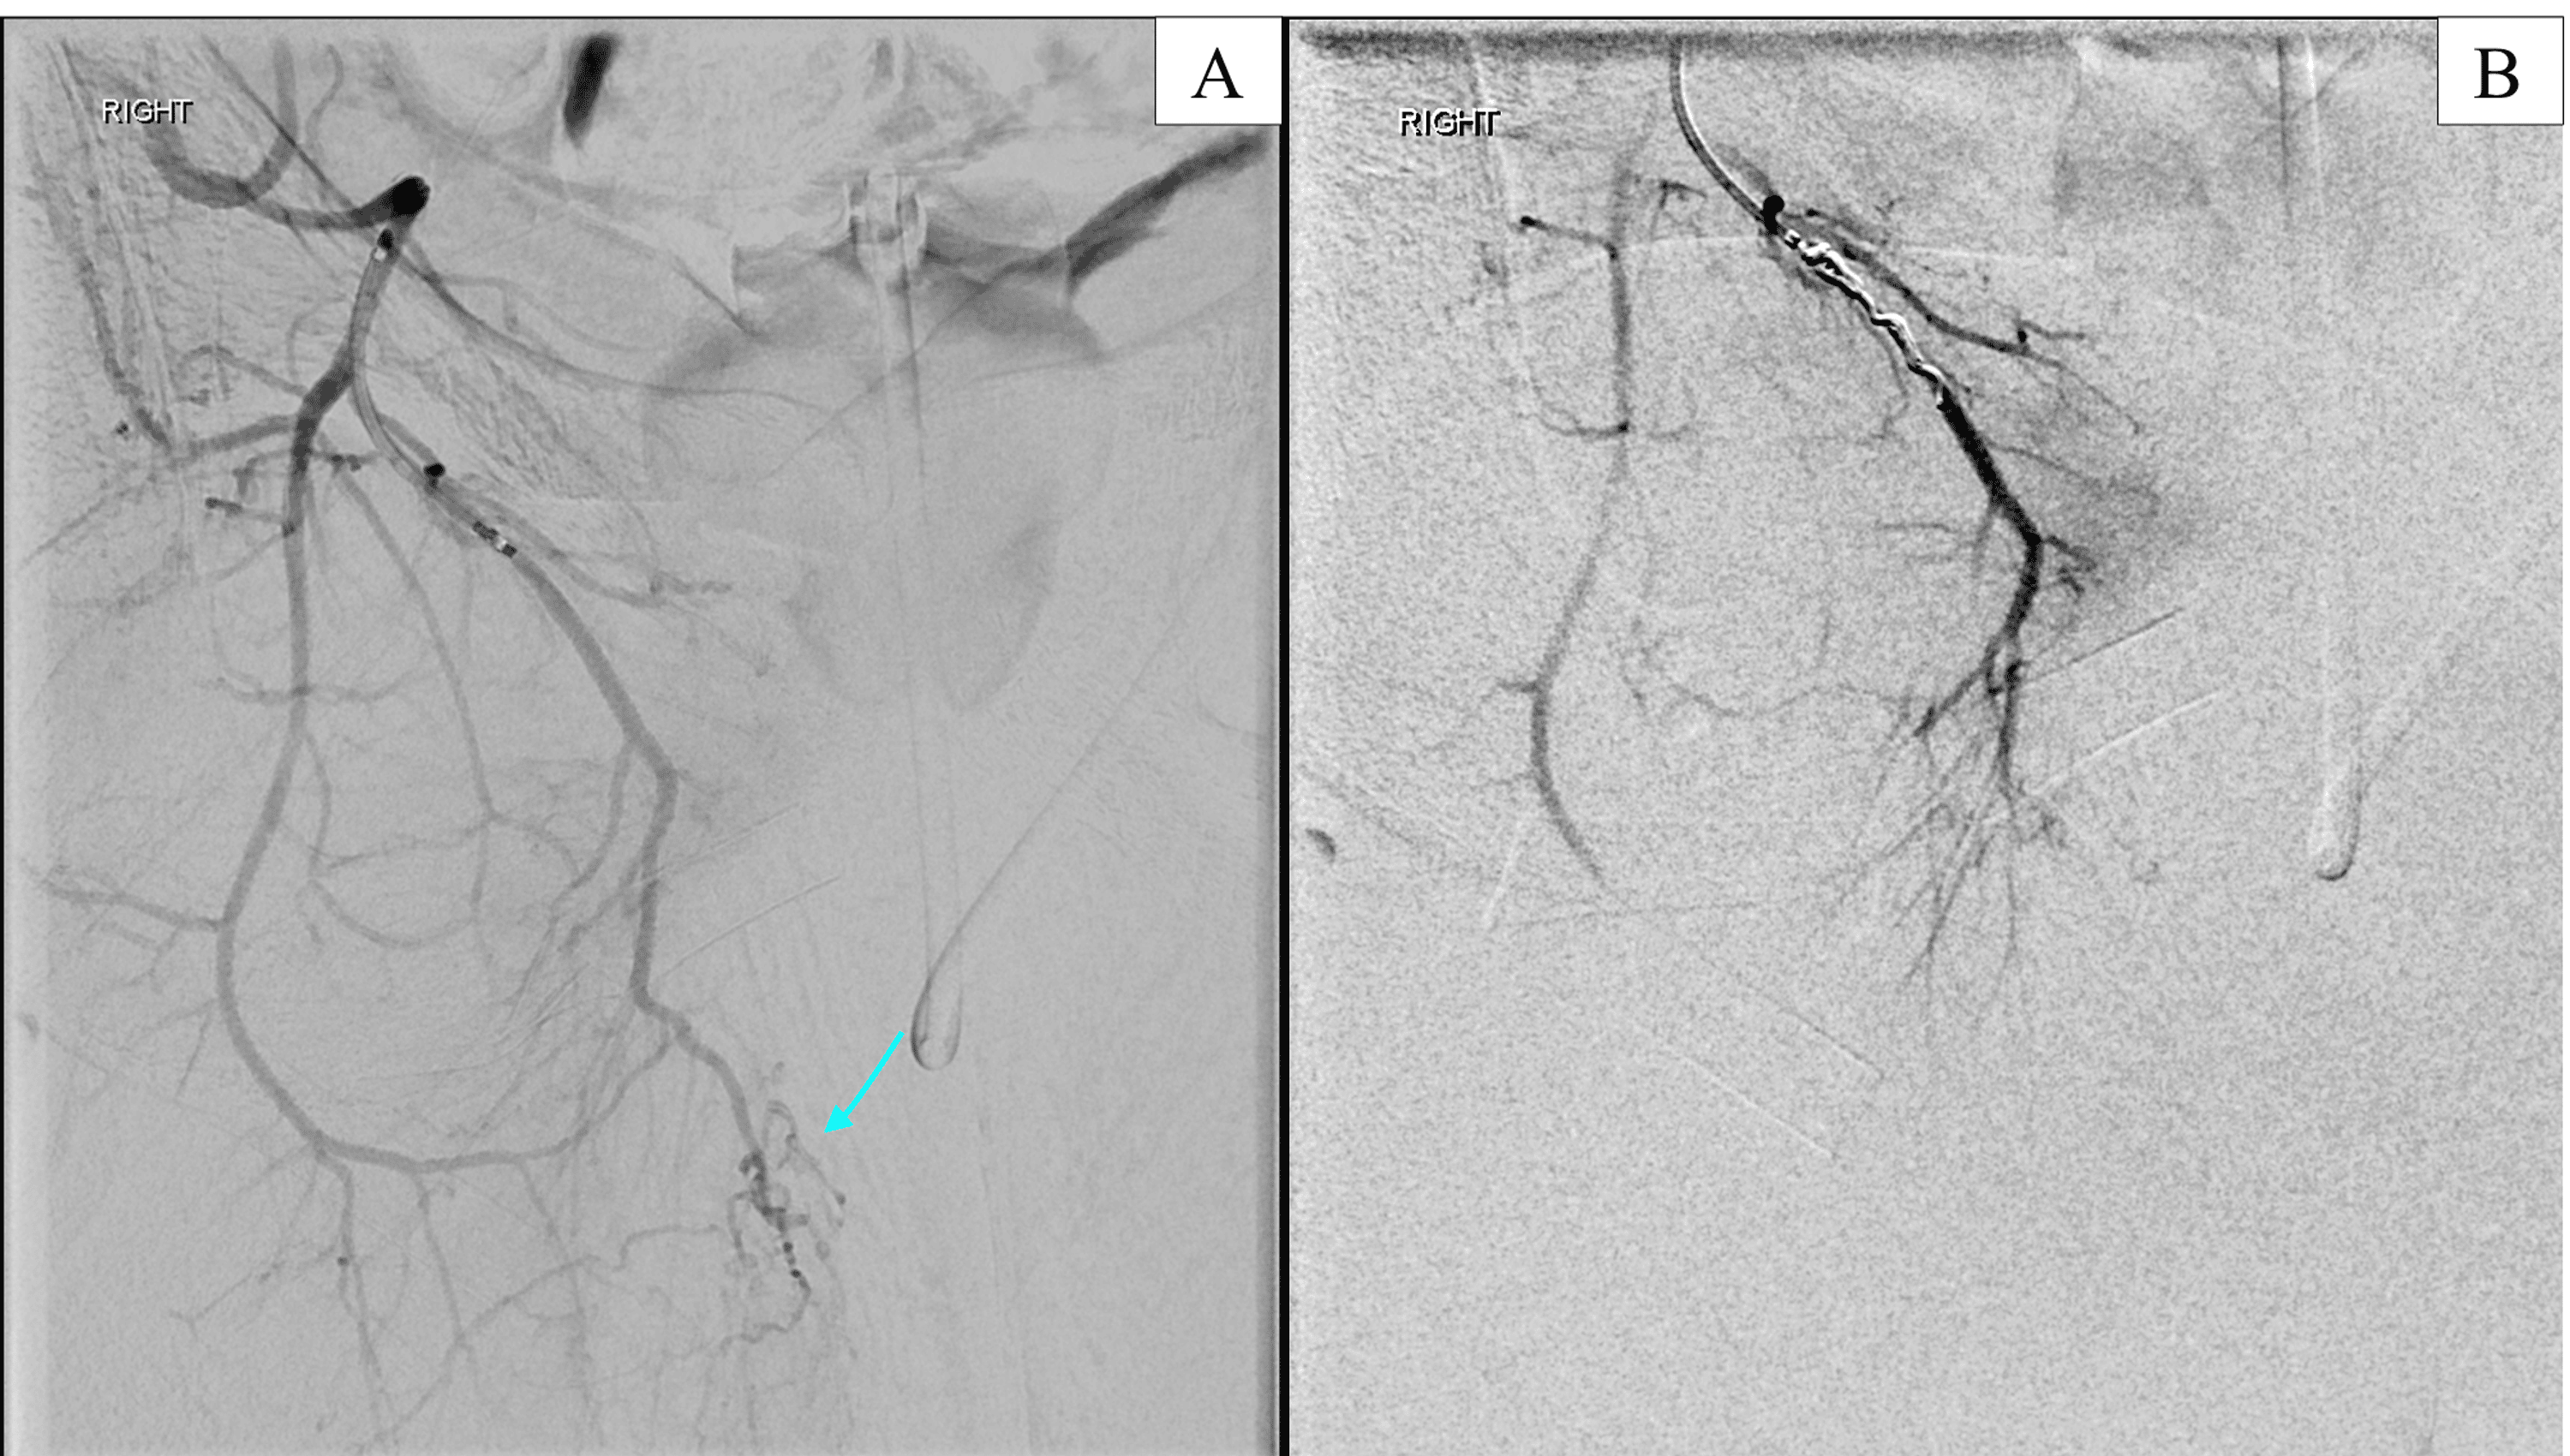

Coil embolization of the collateral pathway (arrow) from the... Download Scientific Diagram Coil Embolization Scrotum  Varicocele embolization is a type of medical procedure. It redirects blood away from an enlarged vein in your scrotum. Varicocele embolization is a minimally invasive procedure which is used to treat abnormal enlargement and dysfunctional veins which. There are several options for the treatment of varicocele, including surgical repair either by open or microsurgical approach, laparoscopy, or. Varicocele embolization is. Coil Embolization Scrotum.

From www.researchgate.net

Embolization coil (arrow) placed in the branch of common femoral artery... Download Scientific Coil Embolization Scrotum  Varicocele embolization is an outpatient procedure with a short recovery time. Coils are commonly used embolic for varicocele, and both detachable and pushable. There are several options for the treatment of varicocele, including surgical repair either by open or microsurgical approach, laparoscopy, or. It redirects blood away from an enlarged vein in your scrotum. Varicocele embolization is a type of. Coil Embolization Scrotum.